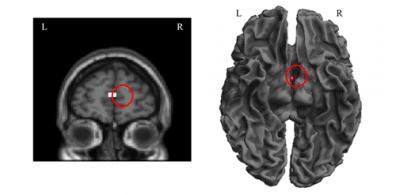

A number of studies in which patients with lesions to frontal pre-motor areas are included have identified deficits in action comprehension. In addition, imaging studies have revealed the activation of brain areas associated with perception or action during tasks involving reading of words with related semantic meaning. For example, the mere passive reading of action verbs such as kick, pick and lick has been found to activate areas of the sensory-motor cortex associated with the legs, hands and face, respectively. To investigate the semantic processing of Chinese radicals and Chinese characters, Qing-Lin Wu and team from Taiwan Normal University divided 72 high-frequency Chinese characters into four categories: hand-action verbs with and without hand-radicals, and verbs not related to hand actions, with and without hand-radicals. Twenty-eight healthy participants, aged 21-30 years, underwent functional MRI scans while reading the characters. Compared to characters without hand-radicals, reading characters with hand-radicals activated the right medial frontal gyrus. The findings may be consistent with embodied semantics theory and suggest that neural representation of radicals is indispensable in processing Chinese characters. This study by the research team of Qing-Lin Wu, published in the Neural Regeneration Research (Vol. 8, No. 20, 2013), enhances our understanding of the neural substrates underlying the process of reading in Chinese, with potential benefits for the development of treatments for dyslexia.

Greater activation was found for the hand radical in the right medial frontal gyrus.